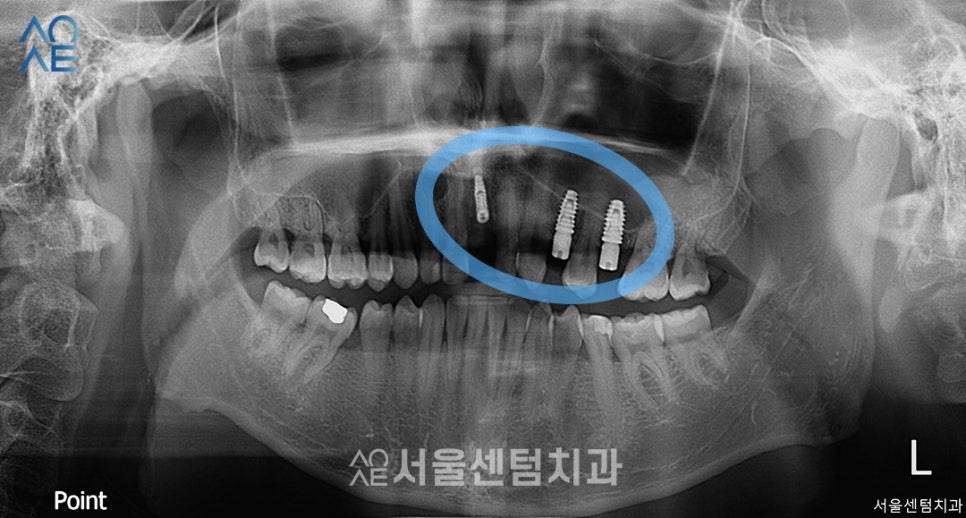

진단과 상담을 마친 후

환자분께서 바로 치료하시길 희망하셔서

당일 식립 수술을 진행했습니다.

이러한 경우엔 시작이 빠르기 때문에

전체적인 치료 기간이 단축될 수 있었습니다.

총 3개를 식립하였고

잇몸 상태가 좋지 않아 뼈이식도 함께 진행했습니다.

또한 왼쪽 윗부분에는 식립을 위한

공간을 만들기 위해 상악동 거상술도

진행해야 했습니다.